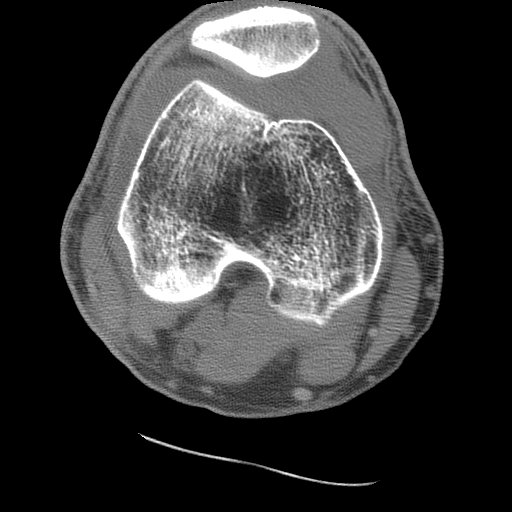

Image 1: Axial CT of the knee (soft tissue window) shows the comminuted fracture of the posterior aspect of the tibial plateau. CLICK TO ENLARGE.

Axial CT examination of a patient with a tibial plateau fracture. CT, like radiography, utilizes x-rays to produce images. As such, CT images generally only demonstrate two levels of a lipohemarthrosis, blood and fat. Attenuation differences between the serum and cellular components is not usually identified by the eye. MRI is required for visualization of all three layers of a lipohemarthrosis.

CASE 1: These two CT images are from the 50 year old male who fell one day prior to presentation. His radiographs and MRI may be viewed as well.